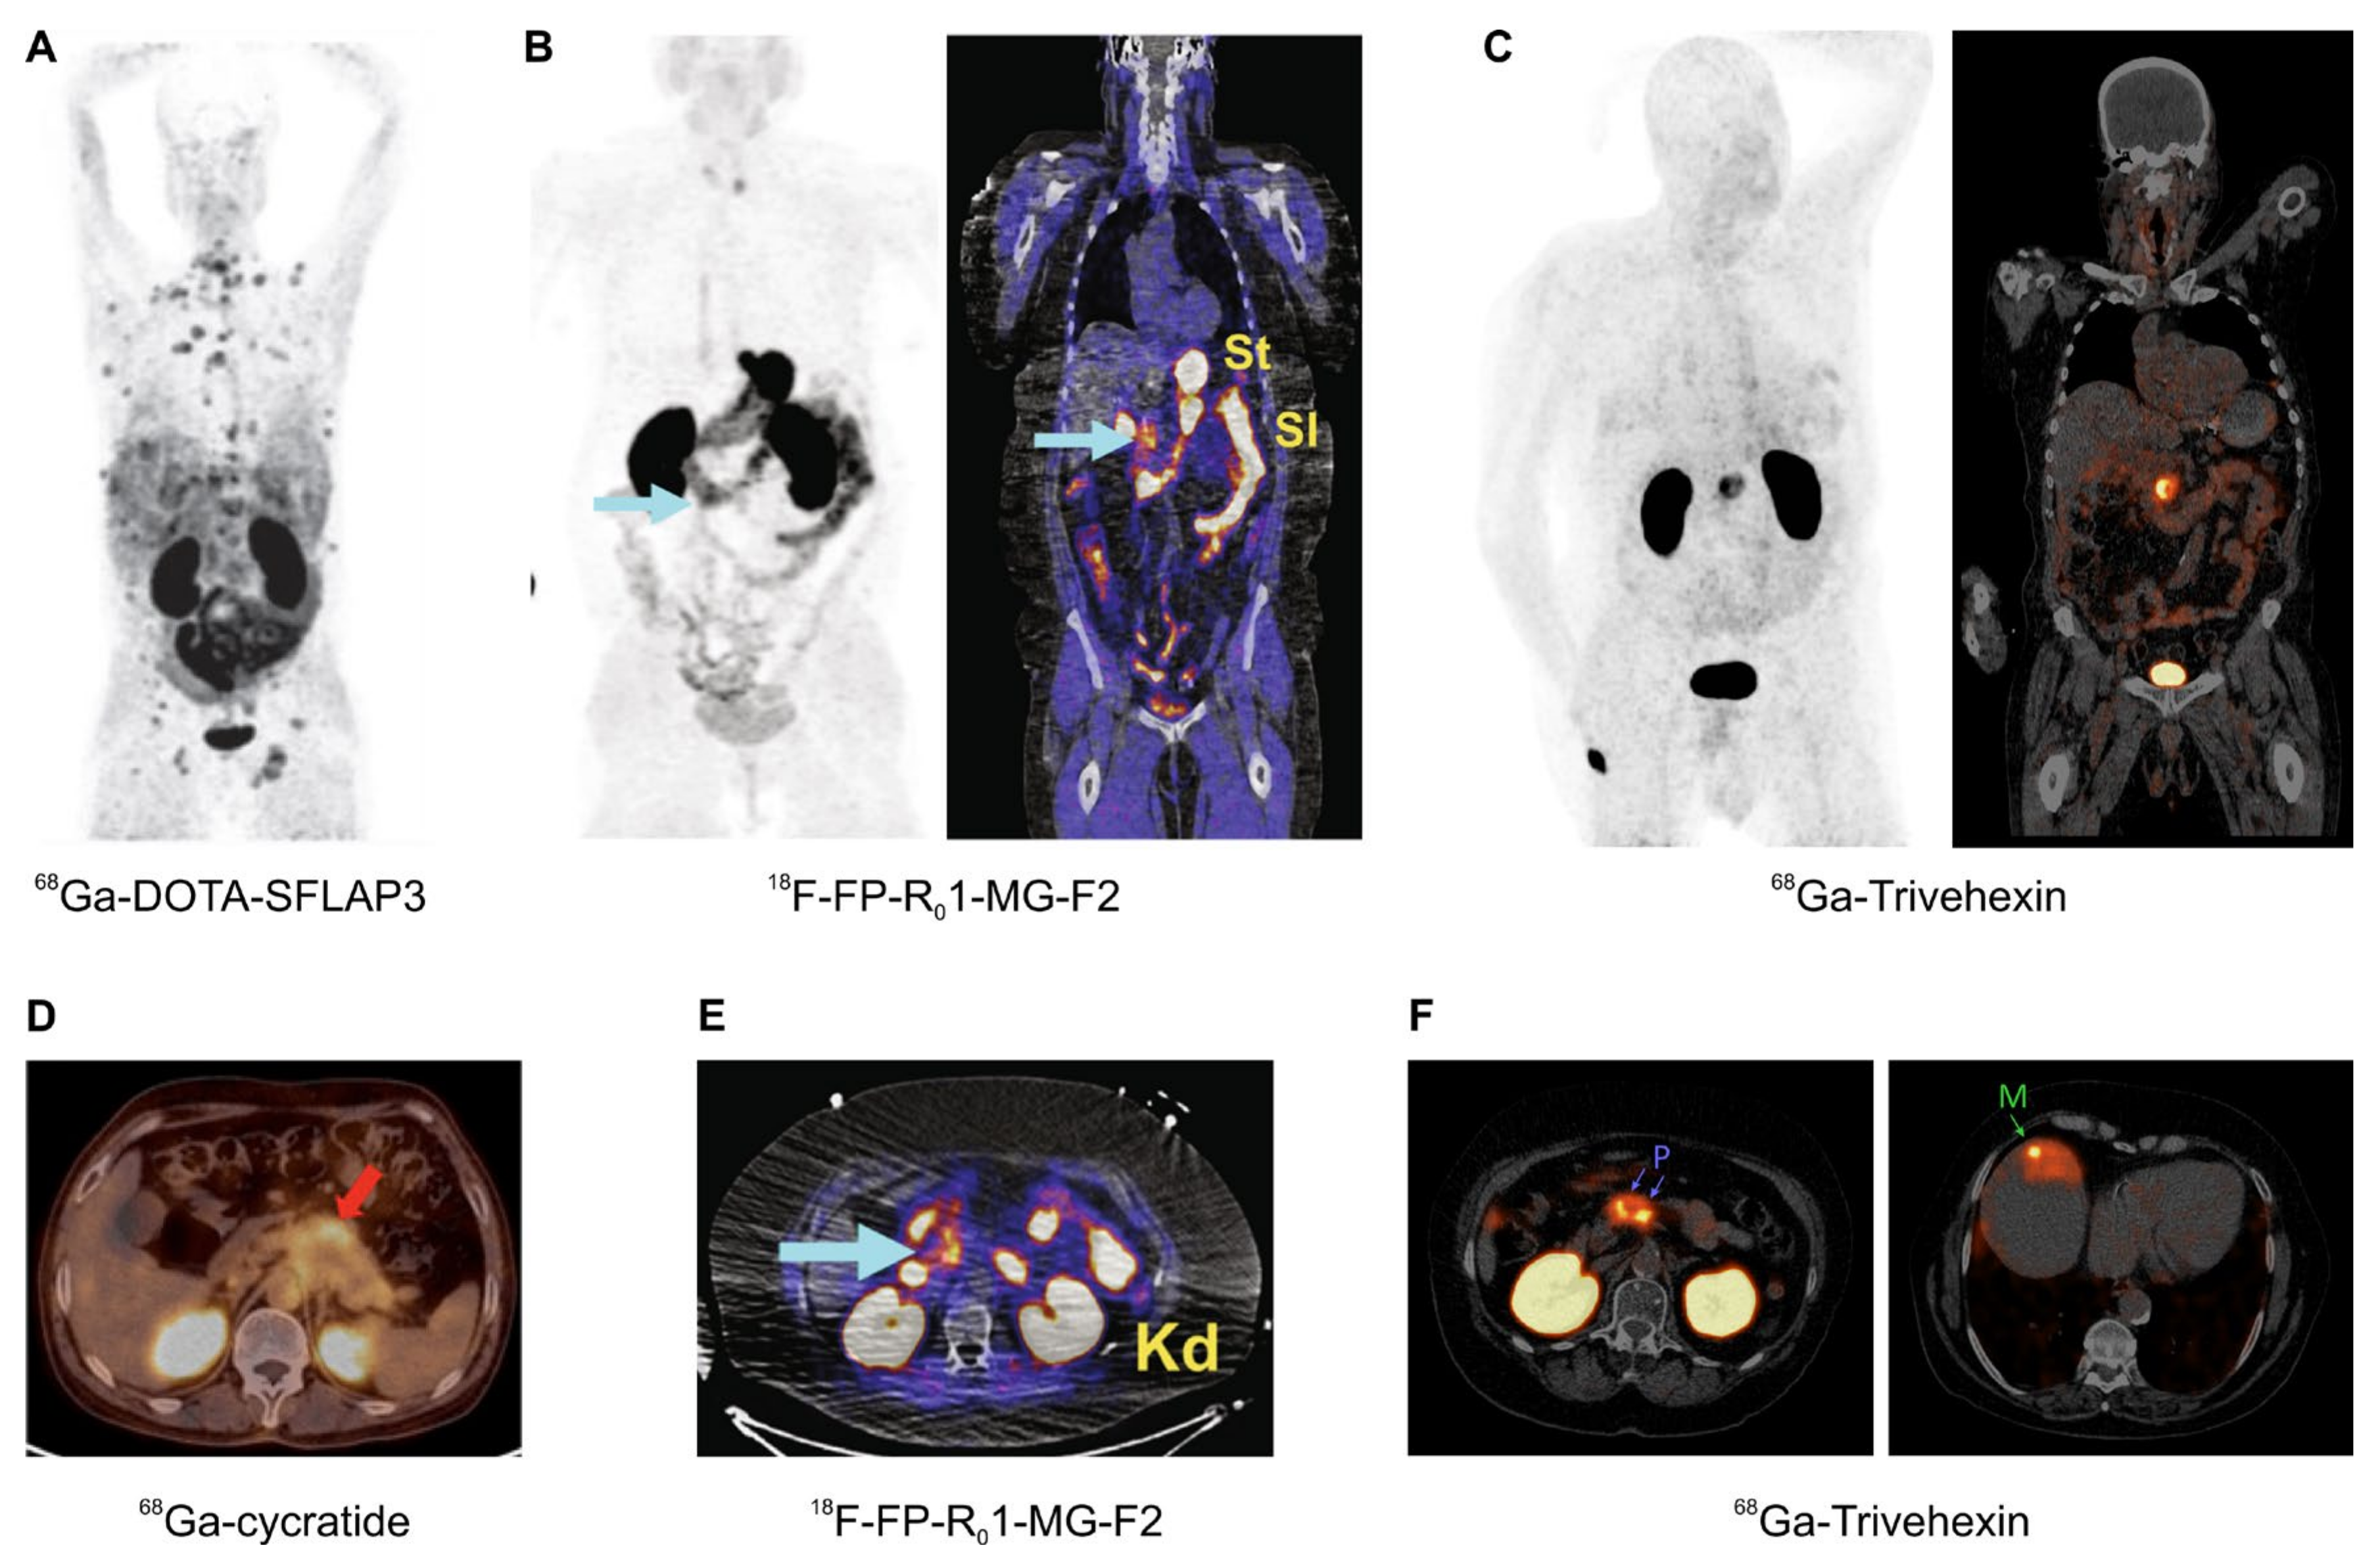

Figure 6.

αvβ6-integrin PET/CT imaging in pancreatic cancer (MIPs (A–C), coronal slices (B,C), and axial slices (D–F); (A–E), 1 h p.i.; F, 2 h p.i.); arrows (wherever shown) indicate tumor lesions. (A): Highly metastatic pancreatic carcinoma, imaged using 68Ga-DOTA-SFLAP3. (B,E): MIP and fusion images of a non-metastatic pancreatic carcinoma, obtained using the knottin peptide based tracer 18F-FP-R01-MG-F2. (C,F): 68Ga-Trivehexin PET/CT of a non-metastatic (C) and metastatic (F) PDAC (“P” indicates the primaries, “M” a liver metastasis). (D): Axial fusion PET/CT of a pancreatic cancer obtained with 68Ga-cycratide. Copyright notice: Images were adapted and reprinted from (A) Nuklearmedizin 2019, 58, 309–18. Müller et al., Preclinical evaluation of peptide-based radiotracers for integrin αvβ6-positive pancreatic carcinoma. [97] © Georg Thieme Verlag KG. (B,E) Nat. Commun. 2019, 10, 4673. Kimura et al., Evaluation of integrin αvβ6 cystine knot PET tracers to detect cancer and idiopathic pulmonary fibrosis [93]; (C) Eur. J. Nucl. Med. Mol. Imaging 2021, 48, 4107–4108. Quigley et al., PET/CT imaging of pancreatic carcinoma targeting the “cancer integrin” αvβ6 [106]; and (F) Eur. J. Nucl. Med. Mol. Imaging 2021, doi:10.1007/s00259-021-05559-x. Quigley et al., PET/CT imaging of head-and-neck and pancreatic cancer in humans by targeting the “Cancer Integrin” αvβ6 with Ga-68-Trivehexin [105]; under Creative Commons CC BY 4.0. (D) This research was originally published in JNM. Feng et al., Clinical Translation of a 68Ga-Labeled Integrin αvβ6–Targeting Cyclic Radiotracer for PET Imaging of Pancreatic Cancer. J. Nucl. Med. 2020;61:1461–1467. [98] © SNMMI.

The most promising field of application arguably is the imaging of pancreatic cancer, because PET imaging of this entity is not reliably possible with the standard tracer [18F]FDG [111]. This applies all the more because PDAC is one of the carcinomas with the worst prognosis, and treatment options are still limited as compared to other malignant cancers, such as prostate carcinoma. A powerful agent for imaging of PDAC might therefore not only be important for diagnostics, e.g., to improve planning of surgery, but also implicates a perspective for future development of targeted radiotherapeutics. An overview of αvβ6-integrin targeted PET/CT with different tracers (Figure 6) corroborates the feasibility of this approach, not only for imaging of PDAC primaries but also of small liver metastases thereof (Figure 6F).

The hitherto reported clinical αvβ6-integrin PET data comprise only a few cases and thus, limited conclusions can be drawn at this stage. The available images of cancers nonetheless clearly indicate a high potential and might, therefore, boost the research in this field, and, above all, trigger the development of the respective radiotherapeutics labeled with the commercially available beta emitter 177Lu, or emerging alpha emitters like 225Ac [46]. This, in turn, is a hopeful perspective for many of pancreatic cancer patients who, in view of a very short overall survival after diagnosis, are in desperate need for novel, improved therapies.